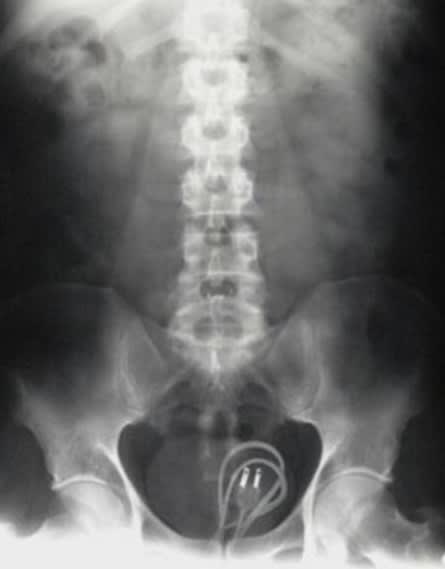

01/09/2017 à 08h21

Manche de pelle 😊😊😊

Img 0293 iy6cb5 - Eugenol

01 ukhwbq - Eugenol

01/09/2017 à 09h28

C'était ambitieux ^^